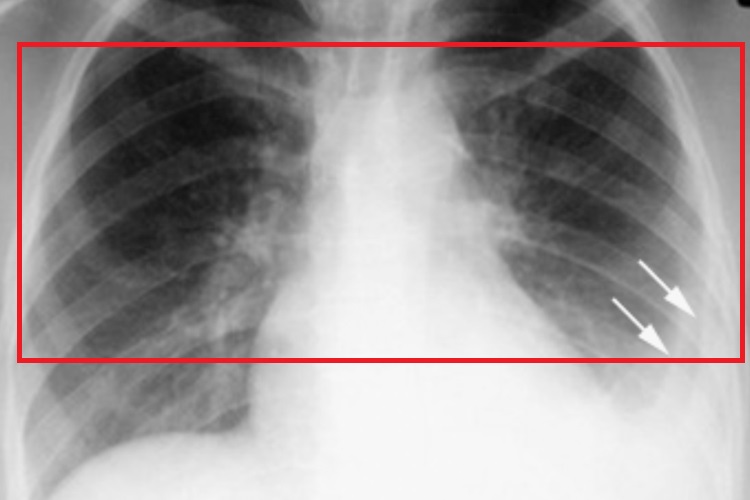

原发性肺结核X线表现为哑铃状的双极影,或肺门区多个或单个的圆形或椭圆形、向外扩展、高密度、边缘模糊的结节影,或呈肺纹理紊乱,肺门形态异常,肺门周围呈结节状、小点片状模糊阴影。患者常有低热、疲乏、食欲不振、消瘦、盗汗、睡眠不安、痉挛性咳嗽等症状。